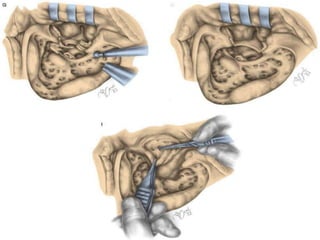

 Crucial components of the procedure include

the following:

 1.Aggressively saucerizing the cavity

 2.Eliminating irregularities within the cavity

(e.g., deep recess and bony overhangs)

 3.Removing the posterior bony canal wall to

the level of the facial nerve

 4.Creating a large meatus.

 Saucerization decreases the depth

and the size of the mastoid cavity.

 The cortical edges of the cavity are

taken down to the approximate level

of the tegmen superiorly, sigmoid

sinus posteriorly, and digastric ridge

inferiorly (Fig.).

 All mastoid air cells should be removed with

exposure of the middle fossa and posterior

fossa dural plates, the sigmoid sinus, digastric

ridge, and bony canal wall (Figure 31-lE).

 Cholesteatoma and granulations filling

the central mastoid tract can be

removed at this time.

 The vertical segment of the facial

nerve should now be identified,

followed by opening of the facial

recess (Figure 31-lF).

 The posterior canal wall can now be safely

taken down with a rongeur and the facial ridge

can be lowered until a thin layer of bone

remains over the vertical segment of the facial

nerve (Figure 31-IG)